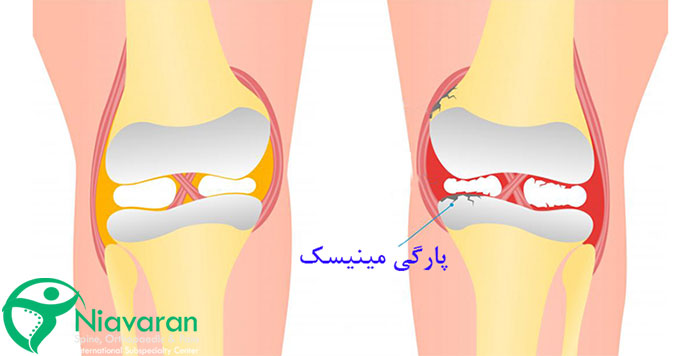

پارگی مینیسک زانو یکی از شایعترین بیماری های زانو است که معمولاً به دلیل پیچ خوردن ناگهانی زانو، چرخش شدید یا فشار زیاد روی مفصل رخ میدهد. این آسیب بیشتر در ورزشهایی مانند فوتبال، بسکتبال و اسکی دیده میشود. همچنین افزایش سن و تحلیل رفتن غضروفها، احتمال پارگی مینیسک را افزایش میدهد. جالب است بدانید افرادی که حرکات ناگهانی و پرفشار انجام میدهند یا دچار ضعف عضلانی در اطراف زانو هستند، بیشتر در معرض این آسیب قرار دارند. پارگی مینیسک ممکن است بهصورت جزئی یا کامل رخ دهد که هرکدام علائم و روشهای درمانی متفاوتی دارند.

علائم پارگی مینیسک کدامند؟

شاید با خود فکر کنید که پارگی مینیسک پا حتما باید در شرایط خیلی حادی اتفاق بیفتد؛ در حالی که حتی ممکن است شما روی زانوی آسیبدیده خود راه بروید و اصلا متوجه پاره شدن مینیسک نشوید. بنابراین حتما به دنبال علائم خیلی عجیب و غریب نباشید. عمدهترین علائم پاره شدن مینیسک، احساس درد پا و سفت شدن آن است؛ اما علائم دیگر آسیب مینیسک زانو، شامل موارد زیر است:

- درد زانو: جزو مهمترین نشانههای این آسیب است. توجه کنید که این درد ممکن است خفیف یا شدید باشد یا حتی به صورت مقطعی اتفاق بیفتد.

- تورم پا: اگر پارگی مینیسک زانو اتفاق بیفتد، زانوی فرد در چند ساعت بعد از آسیب، خود به خود متورم میشود.

- قفل شدن زانو: یکی دیگر از نشانههای آسیب مینیسک زانو، گیر کردن یا قفل شدن زانو است. به این صورت که شما همواره احساس کلیک شدن در زانو پیدا میکنید.

- در هنگام چرخش یا پیچش زانو، درد شدیدی احساس میکنید.

- نمیتوانید به راحتی خم شوید یا این که پای خود را کامل کشش دهید.

- فرد در هنگام پارگی مینیسک، احساس میکند که از زانوی خود صدایی میشوند.

علت پاره شدن مینیسک پا

در حالت کلی، فشار زیاد و پیچاندن زانو، باعث پارگی مینیسک زانو میشود؛ اما ورزشکاران، بیشترین افرادی هستند که در معرض این آسیب قرار میگیرند. خصوصا برای افرادی که در رشتههای ورزشی فوتبال، بسکتبال و تنیس فعالیت میکنند، امکانآسیب دیدگی مینیسک پا بیشتر است. البته لازم به ذکر است که این اتفاق، در بین کودکان هم اتفاق میافتد.

همچنین با توجه به این که مینیسک زانو با بالاتر رفتن سن، ضعیفتر میشود، بنابراین پارگی آن در زانو برای افراد بالای 30 سال، زودتر از دیگر افراد است؛ به طوری که افراد حتی با حرکات ساده هم این صدمه را تجربه میکنند. از طرفی اگر درگیر بیماری آرتروز هستید، بیشتر در معرض پاره شدن مینیسک پا قرار میگیرید.

عوارض پارگی مینیسک زانو

زمانی که آسیب دیدگی مینیسک زانو اتفاق میافتد، تمامی نقاط پا و زانو را تحت تاثیر قرار میدهد. همین موضوع سبب مشکلات مختلفی برای فرد میشود. مثلا ممکن است که شما در نشستن و بلند شدن، احساس درد شدیدی پیدا کنید. همچنین کارهای مختلفی از جمله رانندگی و پیادهروی برای شما خیلی سخت و حتی غیر ممکن میشود. از طرفی با وجود پارگی مینیسک در نوع شدید، امکان سختتر شدن کوچکترین کارهای روزمره هم وجود دارد.